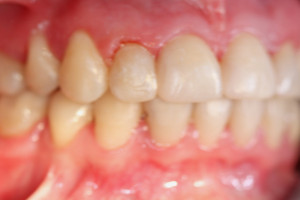

Młoda pacjentka zgłosiła się do naszego gabinetu celem wykonania kompleksowego leczenia zachowawczo-ortodontycznego. Oprócz problemów natury ortodontycznej stwierdzono złą higienę jamy ustnej oraz liczne potrzeby leczenia zachowawczo-endodontycznego. Po wnikliwej analizie telerentgenowskiej oraz analizie modeli zadecydowano o ekstrakcji 2 zębów w łuku dolnym (kła po stronie lewej oraz pierwszego przedtrzonowca po stronie prawej). Plan leczenia obejmował ponadto zamknięcie łuku po brakujących zębach w łuku górnym. Leczenie aktywne trwało 2 lata i 8 miesięcy. W czasie jego trwania pacjentka była regularnie poddawana zabiegom higieny profesjonalnej celem eliminacji zapaleń przyzębia brzeżnego. Po leczeniu aktywnym zastosowano leczenie retencyjne w postaci retainera stałego w żuchwie oraz szyny retencyjnej w łuku górnym.